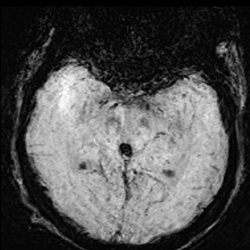

75 yo male with multiple clinical problems (HTN, coronary artery disease) who presented with shortness of breath, nausea and confusion followed by seizures. MR